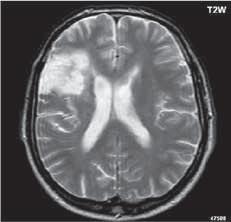

I 2 1 Difuzní astroc ytom low grade

I 2 2

I 2 3

I 2 4

astrocytom